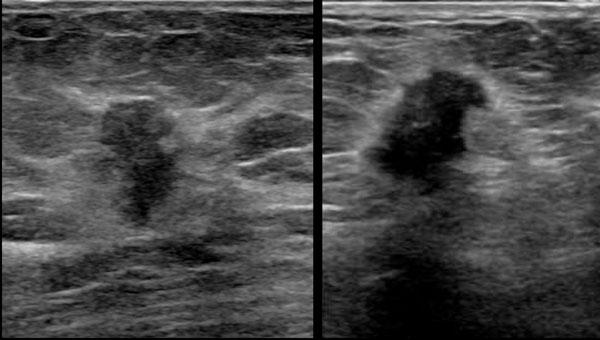

Ung thư vú so với U xơ tuyến vú

Đôi khi ung thư vú có thể có hình ảnh tương tự u xơ tuyến vú và ngược lại, u xơ tuyến vú cũng có thể có hình ảnh siêu âm giống ung thư.

Bảng dưới đây liệt kê các điểm khác biệt về hình ảnh siêu âm giữa hai loại tổn thương này.

Đây là hai tổn thương hình bầu dục giảm âm.

Thoạt nhìn, chúng trông không khác nhau nhiều.

Hãy quan sát kỹ các hình ảnh và xác định những điểm khác biệt.

Tổn thương bên trái là ung thư biểu mô.

- Hình dạng bất thường

- Bờ góc cạnh và không rõ nét

- Quầng tăng âm xung quanh

- Hướng của tổn thương nghiêng về chiều dọc, không song song với da, tức là chiều cao lớn hơn chiều rộng

- Bóng cản âm phía sau

Tổn thương bên phải là u xơ tuyến vú.

- Hình bầu dục với múi nhẹ

- Bờ rõ nét

- Hướng nằm ngang, song song với da

- Tăng âm phía sau